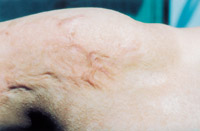

8.深Ⅲ度創(chuàng)面(右大腿及膝關(guān)節(jié)內(nèi)側(cè))自行愈合后3年,瘢痕平整柔軟,無攣縮,不影響功能